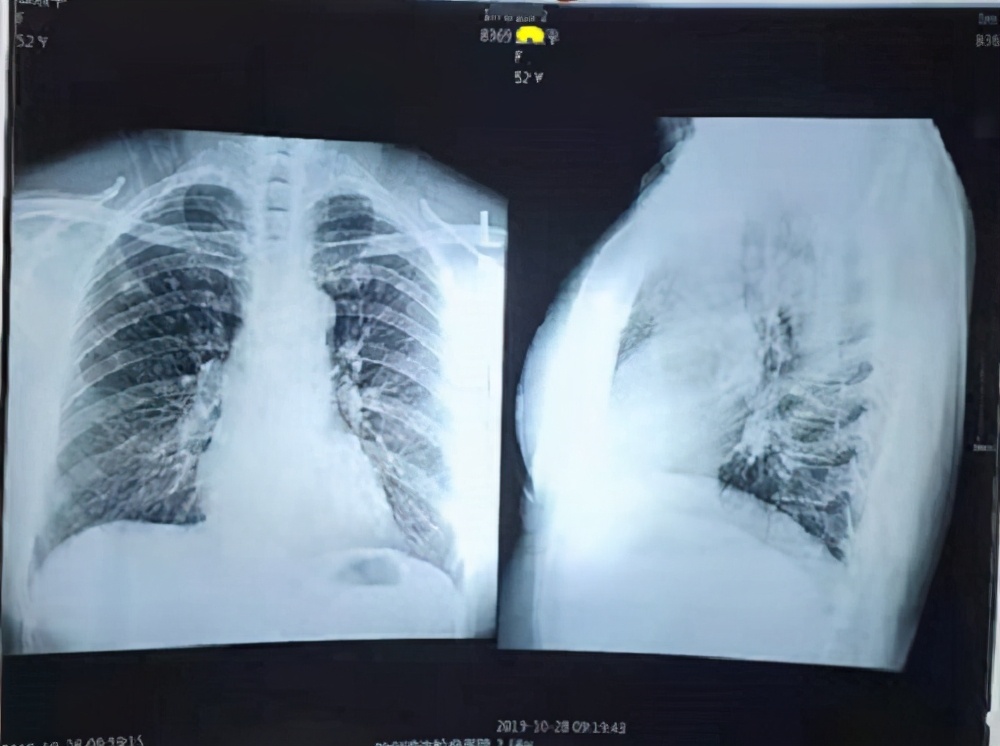

I advised her to get another X-ray. On October 28, 2019, she underwent another DR scan, with the imaging findings showing a patchy nodular proliferative focus in the right upper lung lobe.

Although she interrupted the medication for four months after taking it for a month, the report on her follow-up imaging showed improvement at the lesion site.

I told her: although her condition has improved, it doesn't mean her disease is completely cured, and she should continue taking the medicine for another three months.

This time, she followed my medical advice and conscientiously took the traditional Chinese medicine I prescribed for her for 100 days. During this period, she happened to encounter the COVID-19 outbreak. She was both afraid of taking nucleic acid tests and worried that others might mistake her for a COVID-19 patient, so she did not go to the hospital for testing. She delayed until October 27, 2020, when she finally went to the hospital for a CT scan. The test report indicated bilateral pleural thickening but did not mention the presence of lung nodules. Based on this, it can be concluded that the lung nodule condition had resolved.